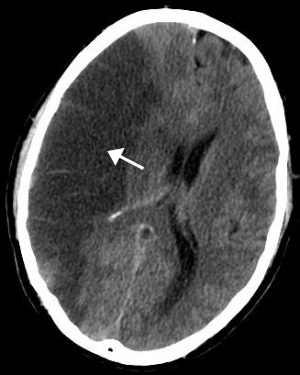

Stroke

Ischemic stroke is increased in both men and women who are obese.[5]

Idiopathic intracranial hypertension

Idiopathic intracranial hypertension, or unexplained high pressure in the cranium, is a rare condition that can cause visual impairment, frequent severe headache, and tinnitus. It is most commonly seen in obese women.[31][32]